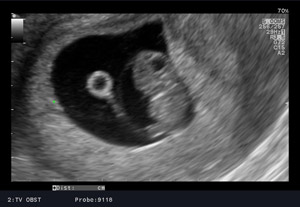

We wczesnej ciąży najlepszy obraz daje sonda dopochwowa. Badanie musi odpowiedzieć nam na pytanie czy ciąża jest pojedyncza, czy mnoga? Czy jest żywa? Czy jest prawidłowo umiejscowiona? Z tego względu badanie USG przewyższa znacznie testy ciążowe. Od 4 miesiąca stosowane są przede wszystkim sondy przez brzuszne. Aktualnie Polskie Towarzystwo Ginekologiczne zaleca wykonanie w ciąży prawidłowej trzech badań USG: około 11 – 13+6 tygodnia ciąży, około 18 - 24 tygodnia ciąży oraz 28 - 32 tygodnia ciąży. Każde z tych badań ma celu ocenę aktualnego rozwoju i dobrostanu płodu. W niektórych przypadkach możliwe jest przewidywanie zagrożenia ciąży na kilka tygodni wcześniej.

USG prenatalne 11 - 13+6 tydzień ciąży

Jest to badaniem przesiewowym wykonywanym między 11 a 13+6 tygodniem (13 tygodni i 6 dni), które ma ułatwić wykrycie zespołu Down’a (trisomii 21 pary chromosomów) i trisomii 18 pary chromosomów. Badanie ultrasonograficzne wraz z badaniami biochemicznymi (białko: PAPP-A oraz wolną podjednostką beta hCG) określa ryzyko wystąpienia wad rozwojowych płodu, pozwala na ocenę rozwoju płodu. W pewnych przypadkach zalecane są dalsze, bardziej szczegółowe badania – oznaczanie DNA płodowego lub amniopunkcję genetyczną i prenatalne badanie ultrasonograficzne między 18-24 tygodniem ciąży.